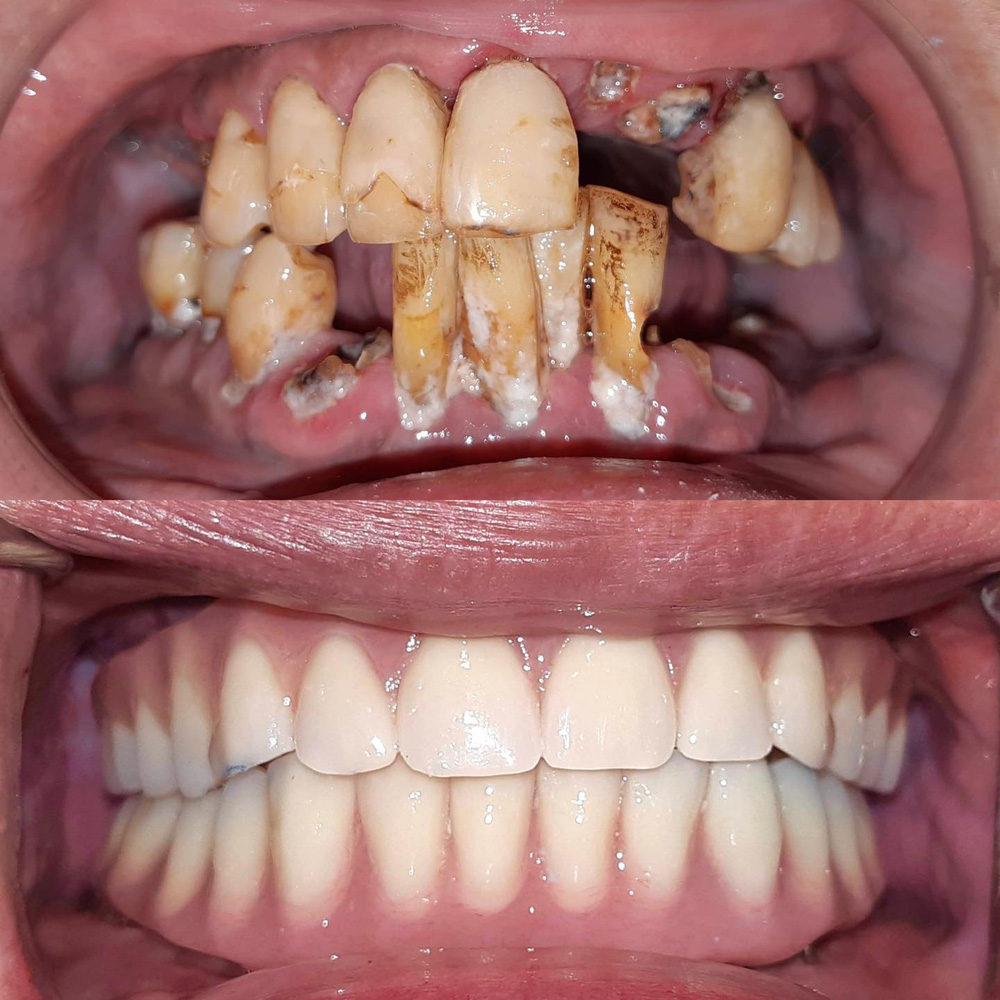

一天 是全口咬合功能及美觀徹底改善需要的時間

全口重建(All on 4/6) 案例